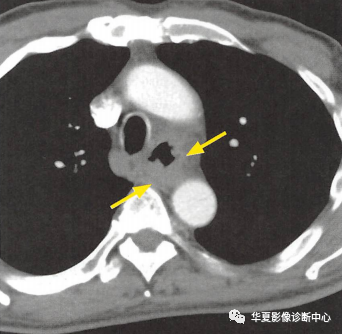

(上图:增强CT食管壁不规则增厚)

①食管壁改变:食管壁全周环形或局部不规则增厚,相应平面管腔变窄或消失,呈肿块样改变;

②食管周围脂肪间隙模糊、消失:提示食管癌向外侵犯;

③周围组织器官受累:多为气管和支气管,常形成食管-气管瘘,其次可侵犯心包膜、左心房和主动脉等;

④转移:以纵隔、肺门及颈部淋巴结转移多见,也可逆行性转移至上腹部淋巴结,少见肺转移。CT增强扫描可见瘤体轻度强化。较大瘤体呈不均匀强化,常合并低密度的坏死灶,较小瘤体强化均匀。

下段食管癌CT图像

下段食管腔消失,呈肿块样改变,平扫呈等密度,增强后有明显强化